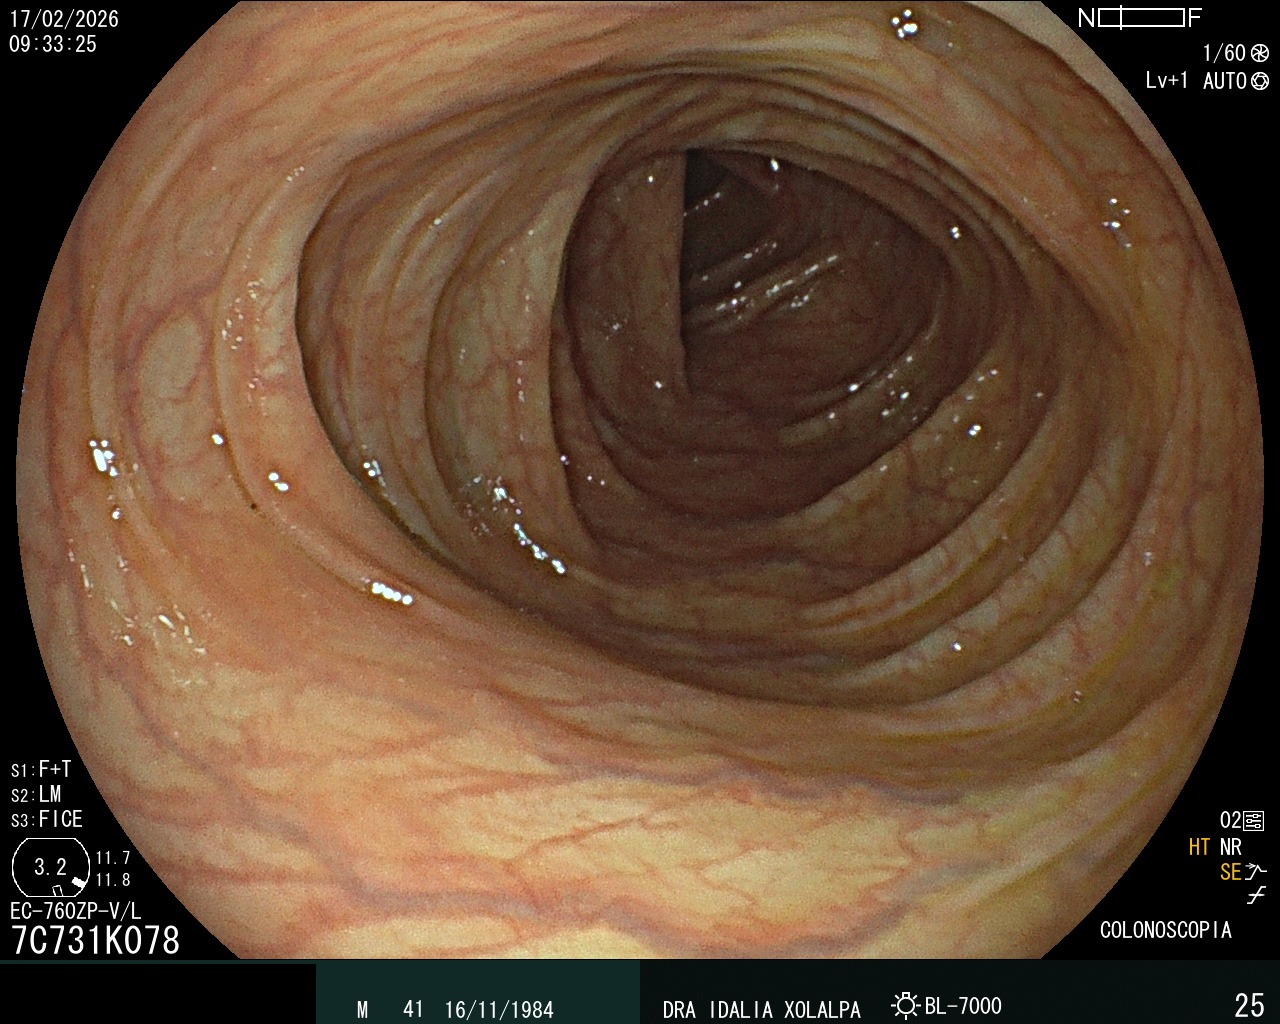

Colon Normal

Vista de un colon sano durante colonoscopia